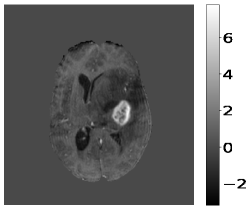

The pre-processing steps on the input MR image and target images are pre-requisites before training the deep learning model. Z-score normalization scales the pixel intensity values of the input MR image to have a mean of zero and a standard deviation of one, and is shown in Figure 2. It is a standard technique in medical imaging to account for variations in image acquisition parameters and to ensure consistent pixel intensity values across different images. The z-score normalization is applied only to brain tissue regions in the MR images, the rest remain unchanged.

The target images have been converted into one-hot vectors. It encodes the segmentation labels as binary vectors, with each dimension corresponding to a distinct label, Edema, NET/NCR, or ET. The normalized input MR images are then stacked. The ground truth and the corresponding one-hot vectors are shown in Figure 3. These pre-processing steps ensure that the input data is in a suitable format for training the deep learning model.